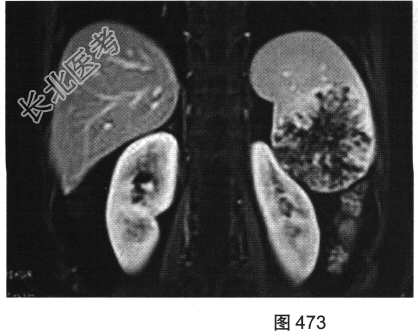

- 多项选择题4.[提示]为进一步明确诊断,患者行MRI检查, 如图470~图473所示。对MRI图像描述正确的是( )

A、T1WI呈不均匀稍低信号

B、左肾被病灶侵犯

C、病灶内见树枝状T1WI低信号、T2WI低信号影

D、门脉期可见造影剂进一步持续充填

E、动脉期轻度强化

F、抑脂T2WI呈不均匀稍高信号